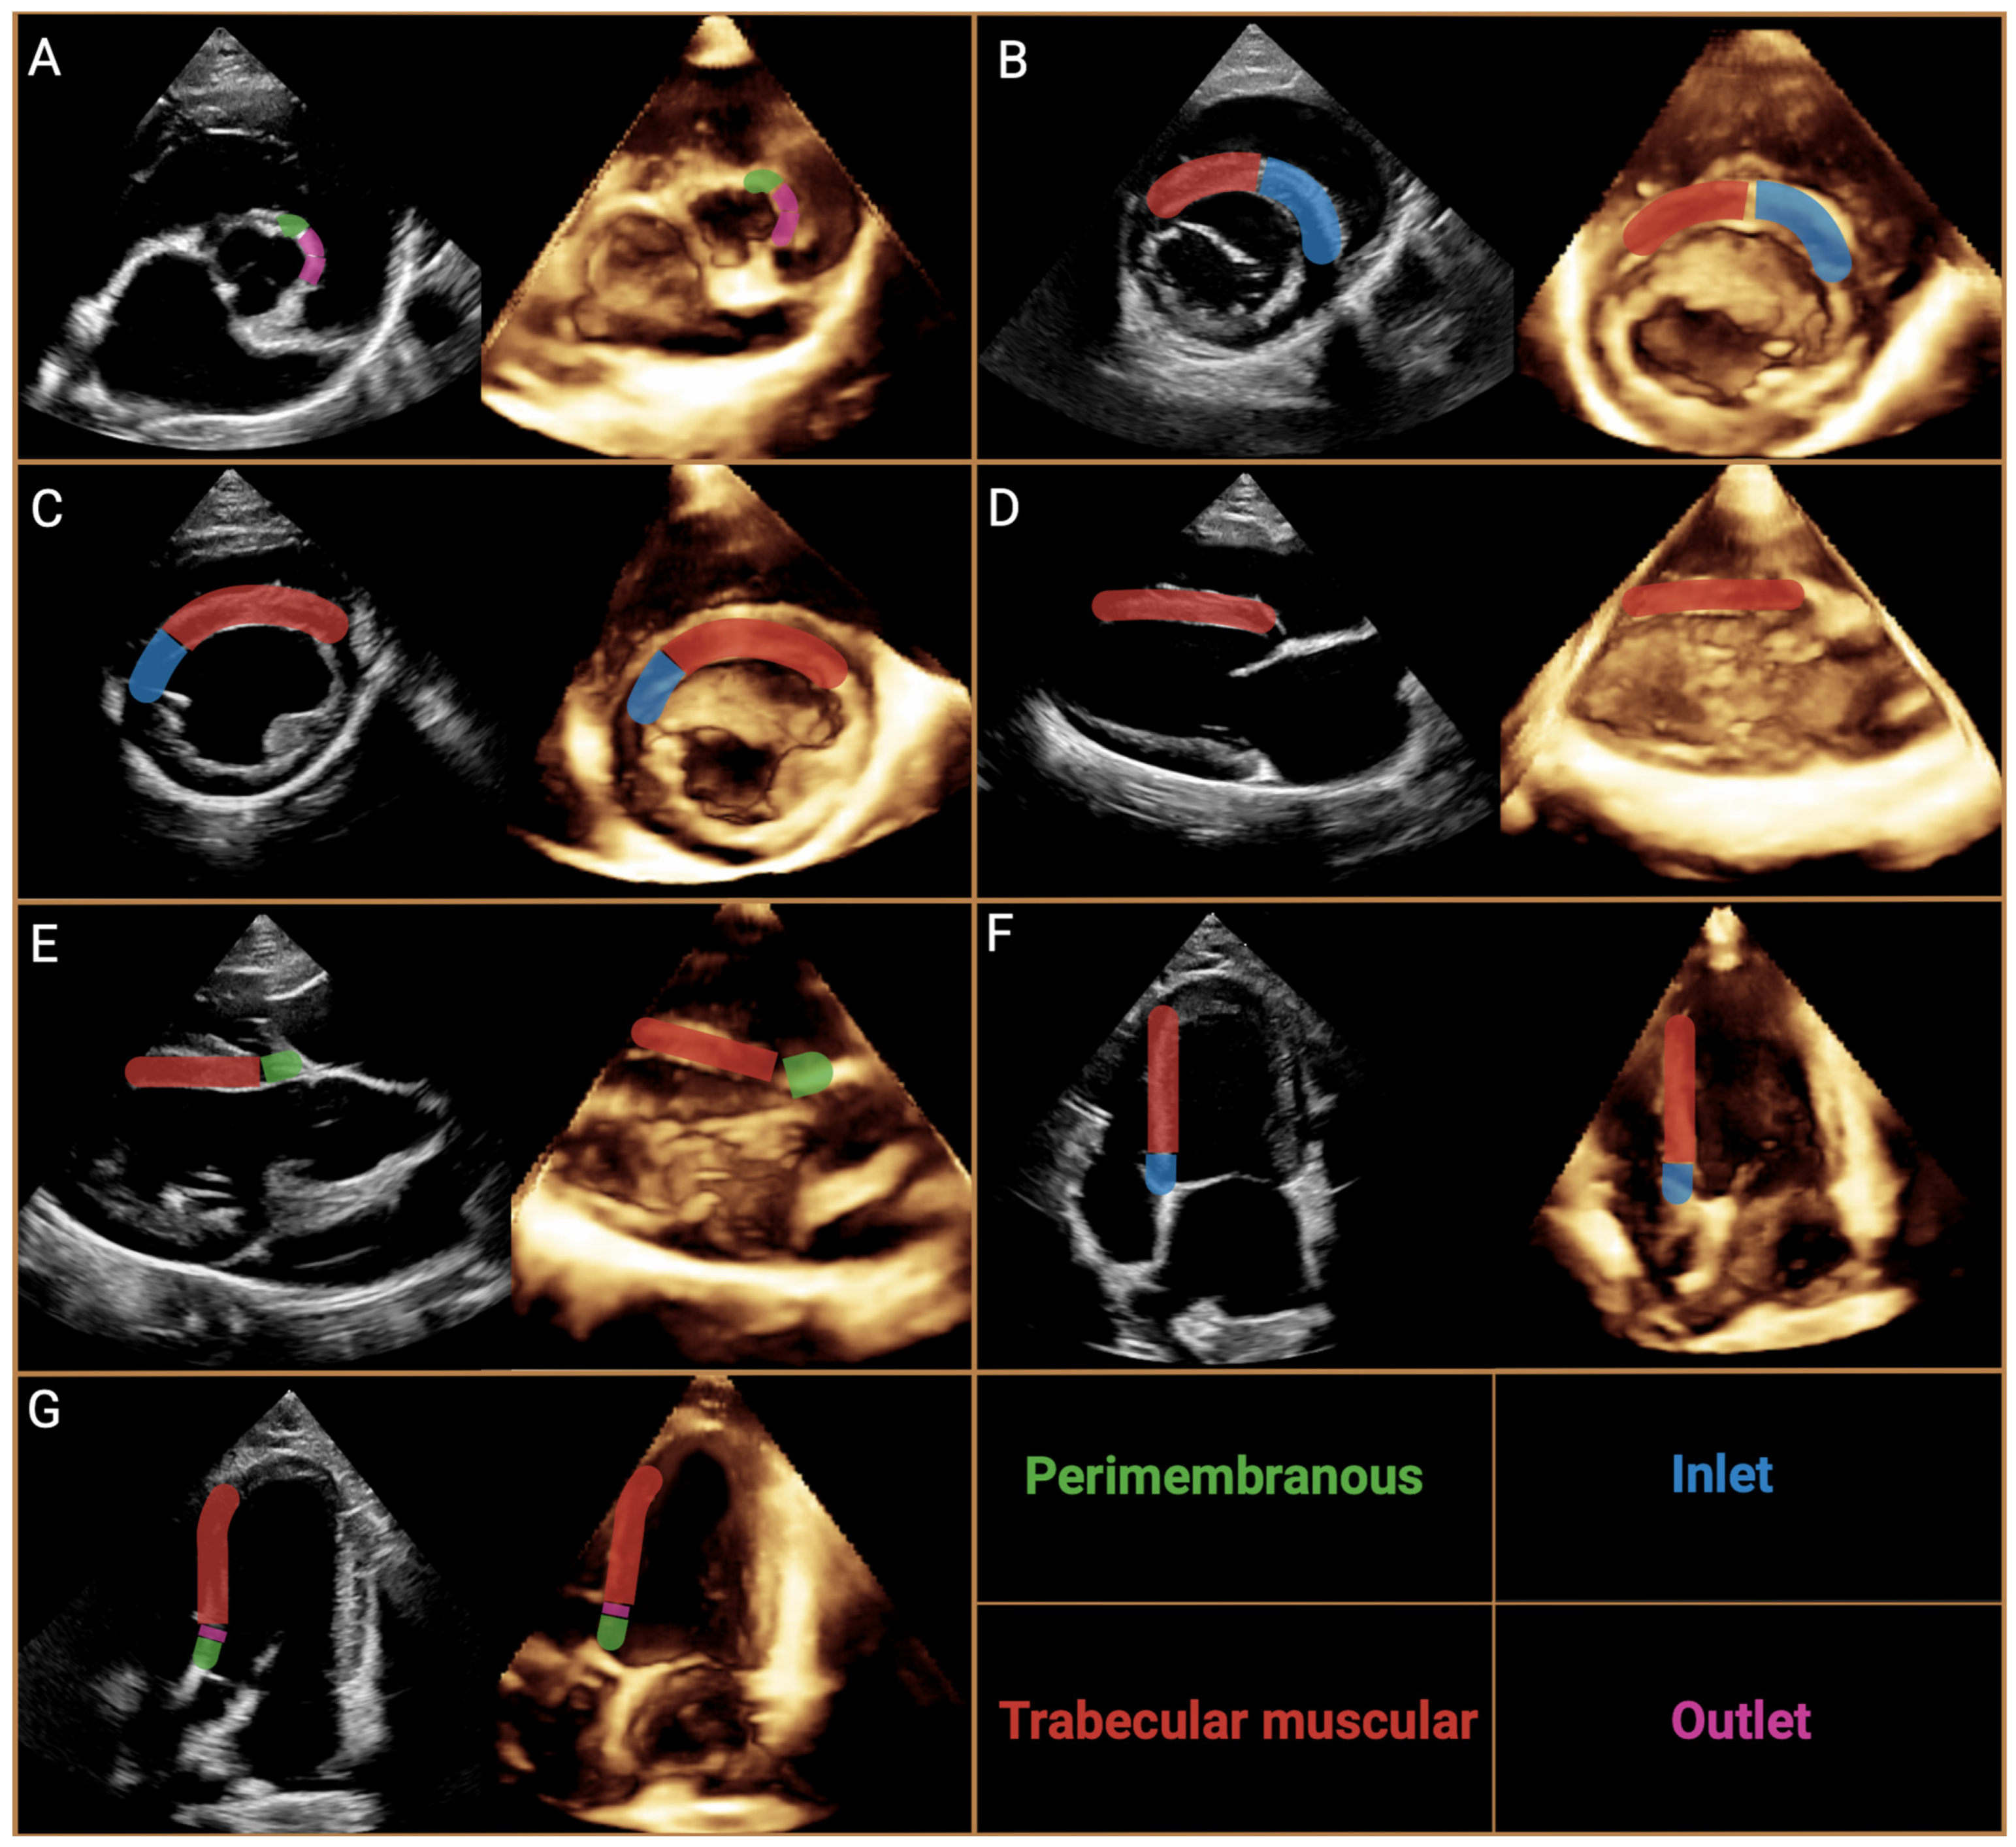

3. Nomenclature of Ventricular Septal Defects

4.2. Echocardiography, Radiography, ECG Findings